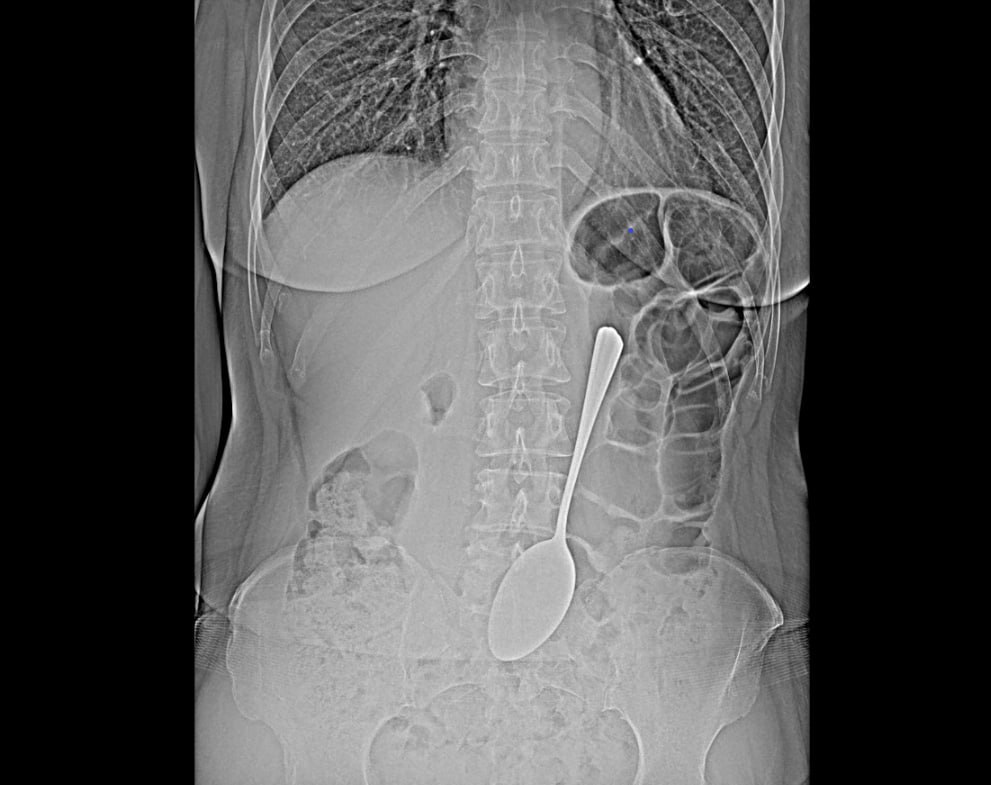

Врачи БСМП в Улан-Удэ извлекли из желудка пациентки столовую ложку

Врачи-эндоскописты провели уникальную операцию - они спасли пациентку, которая проглотила столовую ложку.

Инородный предмет успешно извлекли из желудка с помощью эндоскопа и специальных инструментов. Эта современная методика позволила избежать сложной полостной операции, которая потребовала бы длительного восстановления, пояснили в БСМП.